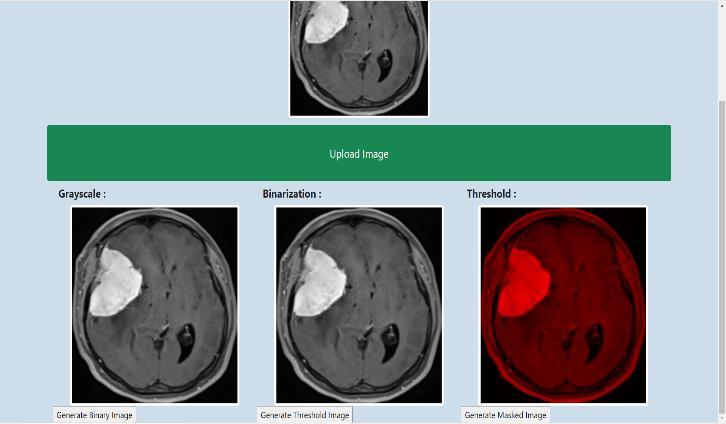

Thereare3stepsinpreprocessing:

1.

Grayscale:

Itconvertsthenormalinputdataintoblackandwhiteimage. Grayscale display the images using only three colors i.e., White,BlackandGray.

2. Binarization:

Binarypictureshavingonlytwovaluesforeachandevery pixel i.e., 0 and 1. It will display the input data as binary valuesi.e.,0and1.

0representsblackcolorand1or255representswhitecolor.

3. Threshold:

Itwillhighlighttheinputdatasothatitwillbehelpfulfor thefurthersteps.

Figure-2: Pre processing